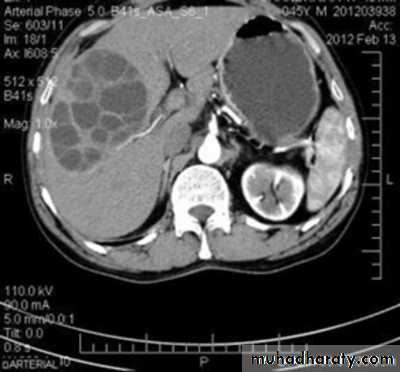

CT abdomen

Hydatid cyst

Appear as large oval hypo dense area density of fluid with well defined margin , sometime at their periphery multiple flecks of calcification are seen at their periphery .

Hydatid cyst with daughter cyst , appear as multiple hypo densities rounded area within the main loculi with multiple rim of

calcification

Secondary metastasis in the liver

Multiple rounded hypo density areas of different density , shape & different size .

Pattern of enhancement is either uniform , target or bulls eye pattern .

Hepato megaly .

Hydatid cyst within the liver